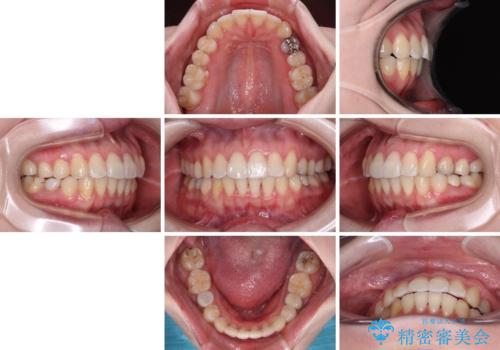

開咬と前方に飛び出した前歯 インビザラインによる矯正治療

- 上下前歯の非接触と叢生を気にして来院された患者様です。

開咬の改善はインビザラインの最も得意とするところであるため、インビザラインを用いて矯正治療を行うこととしました。

舌の突出癖改善のトレーニングをしっかりと行っていただき、上下前歯が接触する咬み合わせを達成することができました。